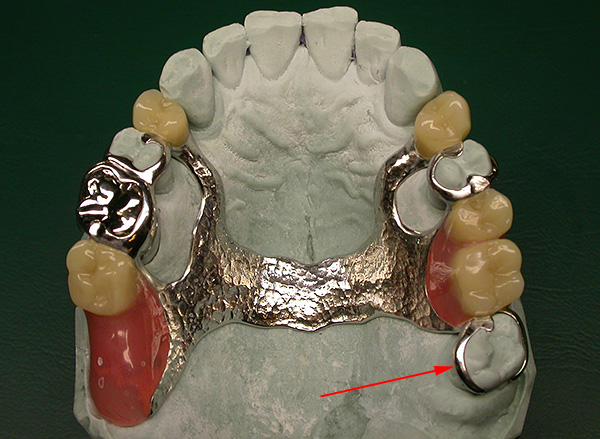

Per quanto riguarda il dente del giudizio, come speranza di una protesi promettente negli anziani, si può dire quanto segue: se un gran numero di denti sulla mascella superiore o inferiore si perde in determinate situazioni cliniche, è la figura otto che può diventare un eccellente supporto per la futura protesi nel senso ampio della parola.

Un esempio di utilizzo di un dente del giudizio conservato come supporto per una protesi di chiusura è mostrato nella foto qui sotto:

Spesso, un dente saggio diventa l'ultima speranza per un ponte - quindi perché, ci si chiede, senza una necessità irresistibile di estrarre un dente del giudizio, che, se si perdono denti importanti per protesi (6 e 7), può diventare un supporto affidabile per il ponte che va dai cinque (premolare).

Anche in caso di distruzione, il dente del giudizio può diventare un supporto sotto la corona e che, a sua volta, fungerà da elemento di supporto per il fissaggio di una protesi parziale rimovibile (fibbia, placca, protesi a farfalla, ecc.).